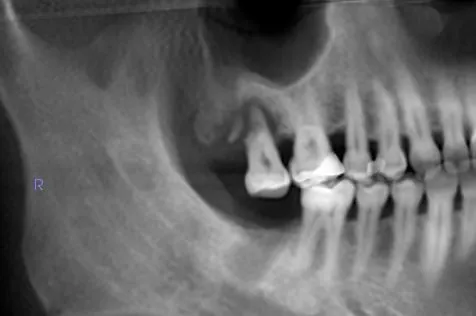

The type of radiation produced by the i-CAT is no different than that produced by any other x-ray machine. But with less radiation, one i-CAT scan can replace all of traditional images like panoramic, a lateral cephalogram (head film) and various periapical x-rays in just one click.

• More details

• Precise location of impacted teeth

• Precise measurement of implant placement

• Bone loss visualization